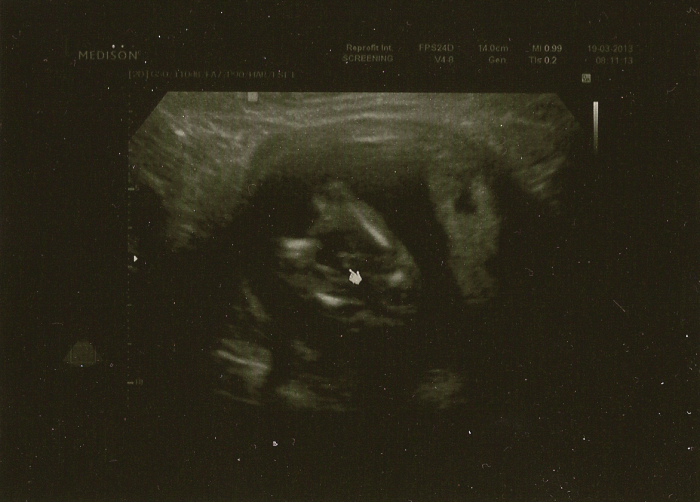

Holky tak já jsem taky po prvotrimestrálním screeningu a jsem nadšená, bylo to ůplně úžasný, vše nám ukazovali a vysvětlovali, mimi je naprosto v pořádku personál skvělý, co to bude ještě nebylo vidět. Jediné co mě mrzí je, že jsem si neřekla o fotku nějak mě to nedošlo, že jí nedávají rovnou jinak bomba. Ale manžel si to vyfotil do telefonu tak nějakou fotku mám.

I já hlásím samé dobré zprávy

... Dle všeho jsme živí, zdraví a pěkně čilí

S tímto vydržím další 4 týdny... Měla jsem to asi jako odměnu za příšerný týden